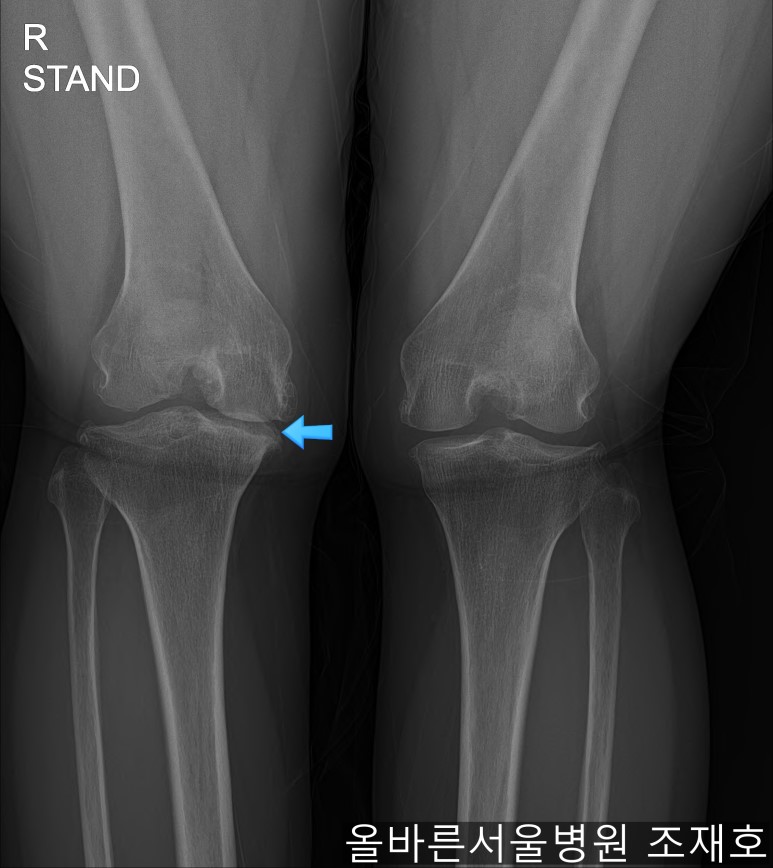

仅通过放射线片子观察到:右膝由于炎症严重,内侧胫骨及股骨已接触在一起,向内测严重变形。

左膝虽然也观察到了炎症,但远不如右膝严重。

如果通过X光片也观察到相同的病症,可以判断内侧关节的软骨大部分都损伤了。